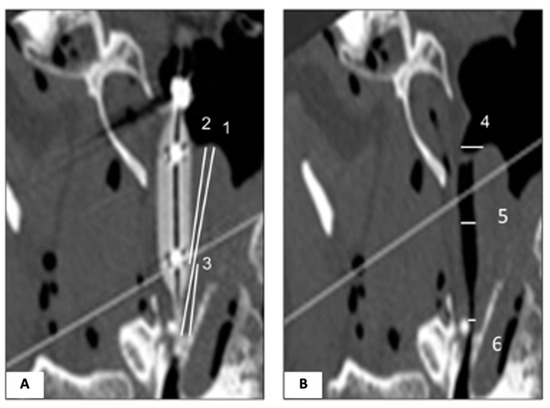

2.2. Experimental Protocol

2.3. Image Analysis